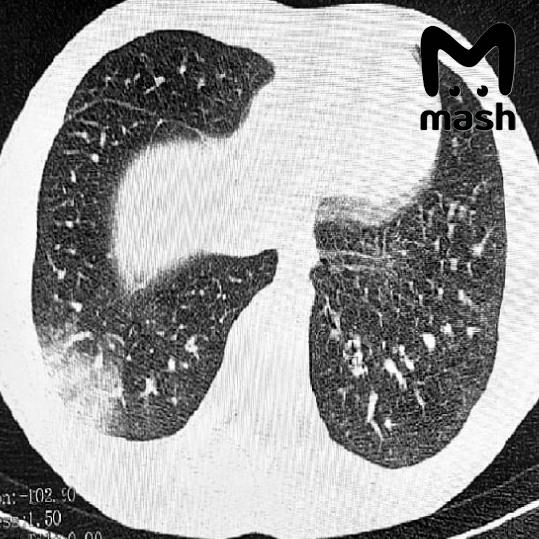

Диагноз EVALI одному из пациентов уже поставили официально. У другого — "токсическое воздействие курительных смесей на центральную нервную систему". Пример пострадавших лёгких — на фото.

Что известно о "попкорновой болезни"? Так называют облитерирующий бронхиолит — заболевание, поражающее бронхиолы. Проявляется в виде воспаления, образования рубцов, сужения бронхиол. Заметить его можно при прослушивании лёгких, которые издают звук, напоминающий треск лопающегося попкорна.